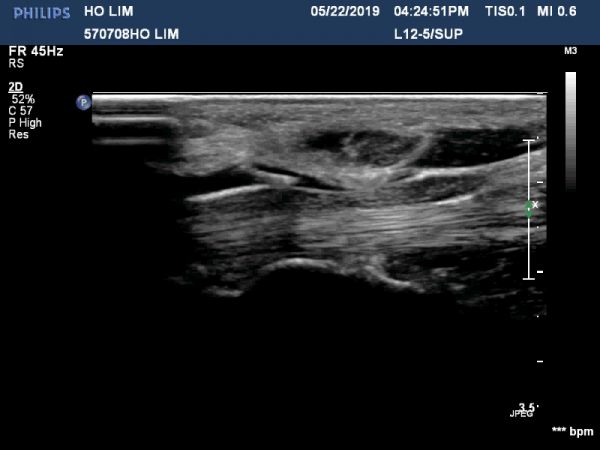

¼ö±Ù°ü ¸»´ÜºÎÀ§(trapezium, capitate level)¿¡¼­ Á¤Á߽Űæ Ⱦ´Ü¸é°Ë»ç»ó Á¤Á߽ŰßÀÇ ÆíÆòÈ­°¡ °üÂûµÊ(»çÁø 3).

Á¤Á߽Űæ Á¾´Ü¸é°Ë»ç»ó ¼ö±Ù°ü ¸»´Ü(trapezium, capitate level)  µÎ²¨¿öÁø È¾¼ö±ÙÀδë(transverse carpal ligament)¿¡

ÀÇÇÑ Á¤Á߽ŰæÀÇ ±¹¼ÒÀû ¾Ð¹ÚÀÌ °üÂûµÊ(»çÁø 4, 5).

ÃÊÀ½ÆÄÀ¯µµÇÏ Á¤Áß½Å°æ ¼ö¾×¹Ú¸®¼ú(÷ºÎ »çÁø Âü°í)  »çÁø¿¡¼­ Á¤Á߽ŰæÀÇ Ç¥Ãþ¿¡ ÁÖ»ç¹Ù´ÃÀÌ À§Ä¡Çϰí

ÁÖ»çµÈ ¼ö¾×¿¡ ÀÇÇÑ È¾¼ø±Ù Àδ밡 Á¤Á߽Űæ°ú ºÐ¸®µÇ´Â ¸ð½ÀÀÌ º¸ÀÓ(»çÁø 6, 7, ÷ºÎÆÄÀÏ µ¿¿µ»ó). ½ÃÇàÇÏÁö ¾ÊÀ½.